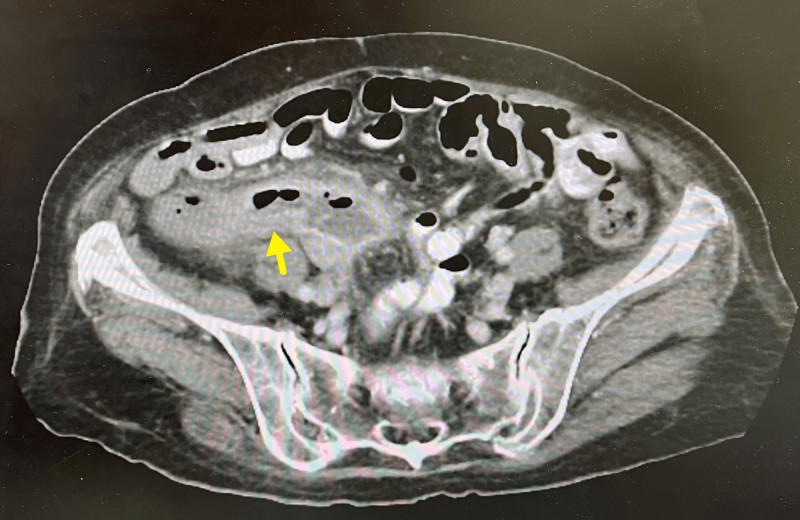

健康網》排便老是排不乾淨?竟罹罕見「同時性大腸癌」 這族群注意

2026/03/15 20:09一名病患半年來一直覺得怪怪的,頻跑廁所總覺得排不乾淨,有時一天要跑好幾趟廁所才行,他自覺體重沒有下降,食欲不錯,應該沒什麼大問題。肝膽腸胃科醫師張振榕指出,大腸鏡檢查竟發現兩處腫瘤,確診為罕見「同時性大腸癌」。他警告,發生率約佔所有大腸癌病例之3–5%,好發於高齡族群及男性。